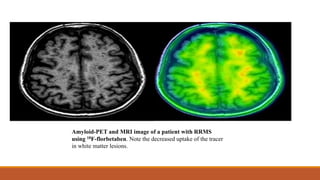

Positron Emission Tomography

Positron emission tomography (PET) uses radioisotopes that directly

bind to different tissue substrates to enable molecular imaging.

18F-florbetaben derivative has an affinity for CNS myelin and

demonstrates differential binding to normal and demyelinated white

matter.

Amyloid-PET and MRI image of a patient with RRMS

using 18F-florbetaben. Note the decreased uptake of the tracer

in white matter lesions.